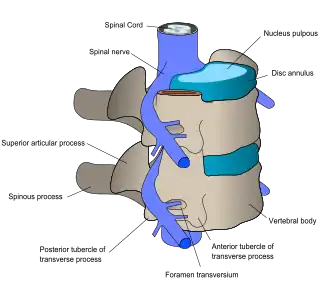

At each level of the spinal column, spinal nerves branch off from either side of the spinal cord and exit between a pair of vertebrae, to innervate a specific part of the body. The area of skin innervated by a specific spinal nerve is called a dermatome, and the group of muscles innervated by a single spinal nerve is called a myotome. The part of the spinal cord that was damaged corresponds to the spinal nerves at that level and below. Injuries can be cervical 1–8 (C1–C8), thoracic 1–12 (T1–T12), lumbar 1–5 (L1–L5),[9] or sacral (S1–S5).[10] A person's level of injury is defined as the lowest level of full sensation and function.[11] Paraplegia occurs when the legs are affected by the spinal cord damage (in thoracic, lumbar, or sacral injuries), and tetraplegia occurs when all four limbs are affected (cervical damage).[12]